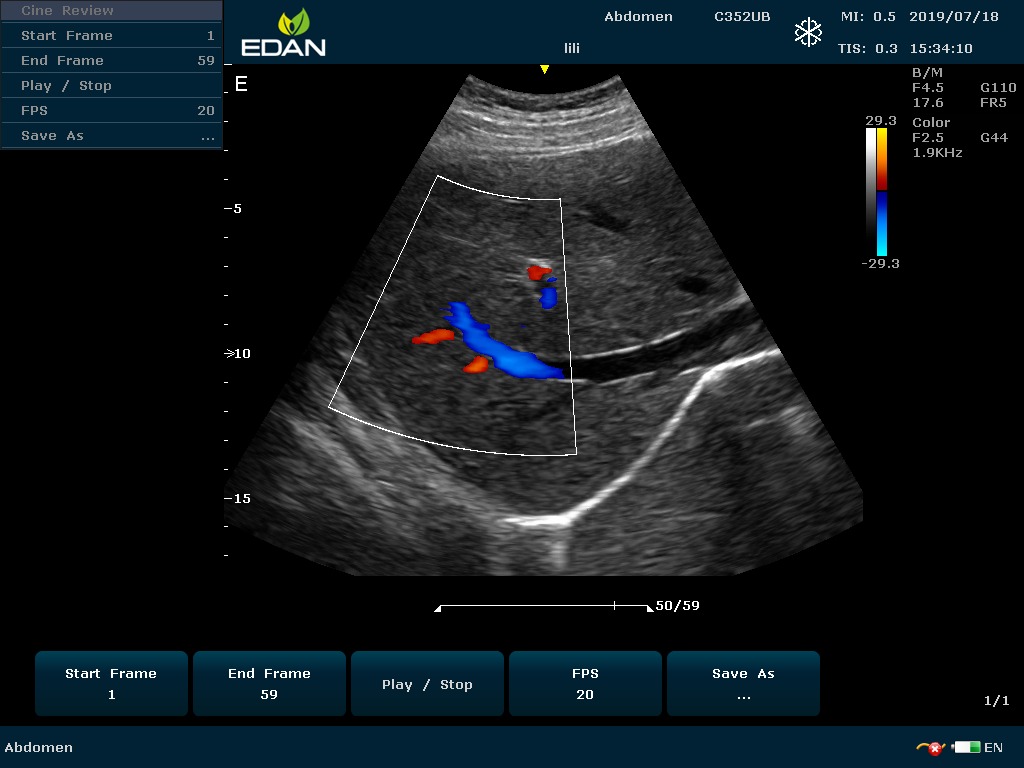

Особенность U60 Edan — расширенное применение. Ультразвуковой аппарат рекомендован для абдоминальных исследований, гинекологии и акушерства, кардиологии, педиатрии, урологии, изучения малых органов, сосудов. Для U60 Edan используются конвексные, линейные, фазированные и внутриполостные датчики.

Передовые технологии позволяют повысить качество визуализации в несколько раз. УЗИ-аппарат U60 Edan отличается возможностью быстрой настройки визуализации. Специальные функции позволяют моментально отображать данные за счет быстрой оптимизации параметров. Режимы визуализации: B-mode, M-mode, Color Doppler, Power Doppler Imaging, Pulsed Wave Doppler, Continuous Doppler.

• Цветовое Допплеровское картирование

• Импульсная Допплерография